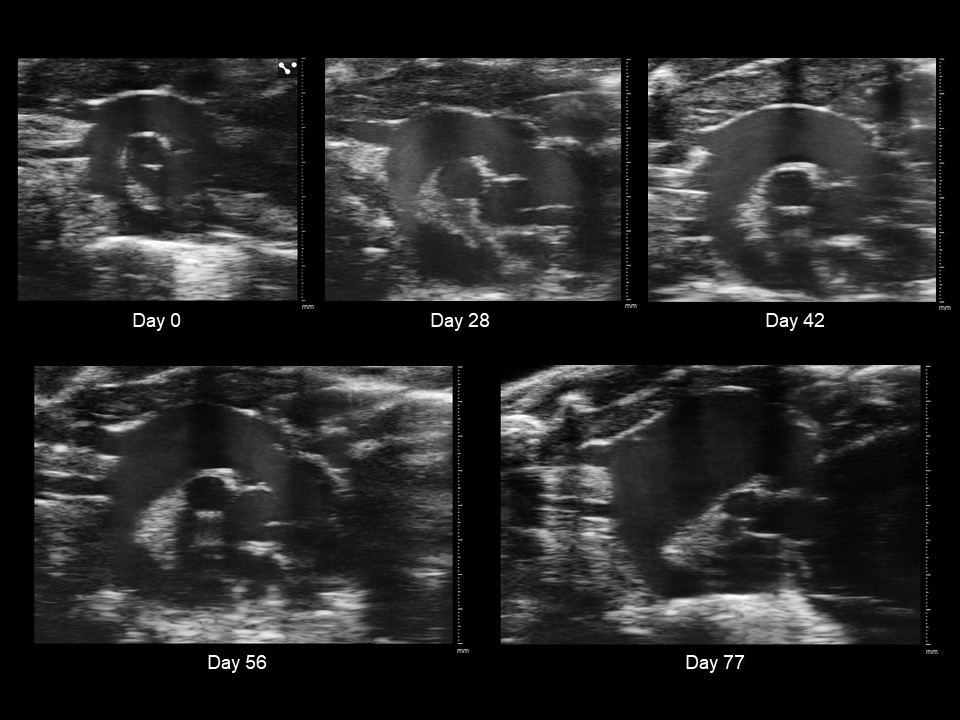

Progression of a Murine Thoracic Aortic Aneurysm

Submitted by: Ethan Kelley

Category: Anatomy & Physiology

Contributors: Cortland Johns

Creation: EKV (EKG-gated Kilohertz Visualization) Ultrasound Imaging

Caption: EKV ultrasound imaging visualizes the progression of a murine thoracic aortic aneurysm through five-time points after the introduction of BAPN (beta-aminopropionitrile) to drinking water. BAPN inhibits collagen replacement around major arteries, causing aneurysms when administered to young mice. Major tick marks indicate millimeters. Images were collected and processed with VisualSonics Vevo3100 and Vevo Lab.